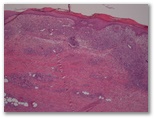

1437-R4-Paciente 75 a , con lesiones tumorales aisladas 2-3, infiltradas. CD3+/CD4+/-, CD30-neg, CD56 –neg, TIA1+

a. Linfoma anaplasico

b. Papulosis linfomatoide

c. Linfoma NK

d. Leucemia de células dendríticas